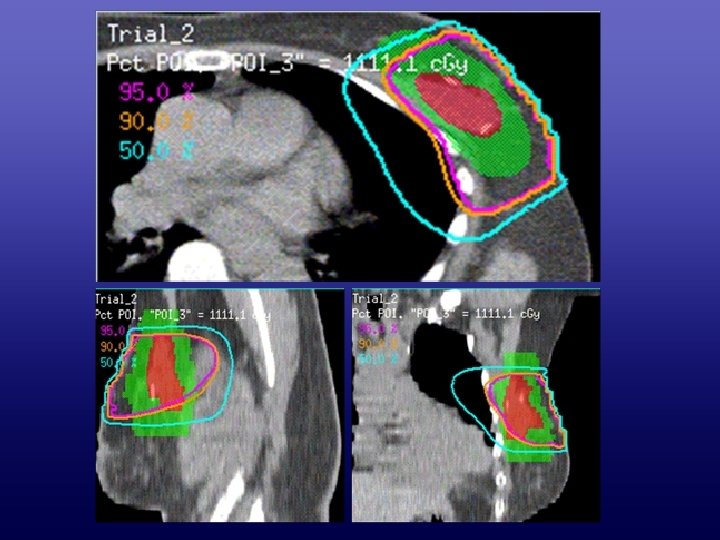

3 DCRT • 6 MV photon beam • 3 fields • Optimized gantry angle

3 DCRT • 6 MV photon beam • 3 fields • Optimized gantry angle and wedge direction • 95% isodose emcompassed the TB-PTV 复旦大学附属肿瘤医院